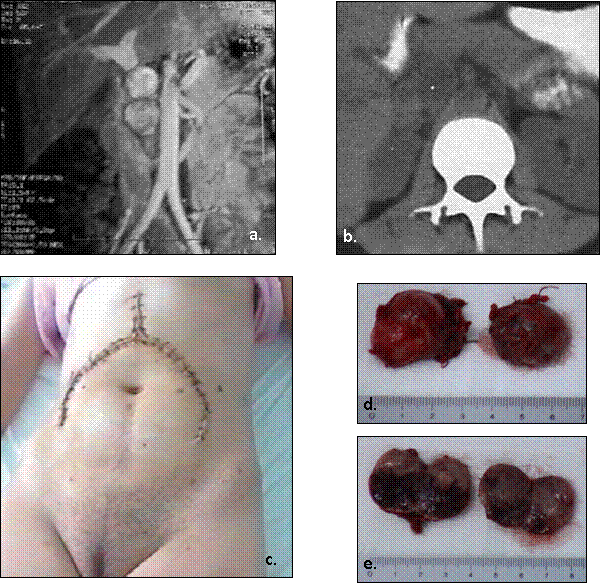

Fig.10. Feocromocitoame bilaterale multiple în cadrul sindromului MEN IIa

(piese operatorii).

Fig.11. Feocromocitoame bilaterale multiple, în cadrul sindromului MEN IIa

(studiu microscopic).

MEN IIb (sau MEN III) asociaza:

Fig.12. Feocromocitoame bilaterale multiple, în cadrul sindromului

MEN IIb (MEN

|

Fig.13. Feocromocitoame bilaterale multiple, în cadrul sindromului MEN IIb - pete pigmentare în regiunea inghinala. |

Fig.14. Feocromocitoame bilaterale multiple, în cadrul sindromului

Feocromocitom multiplu. a) aspect RMN; b) aspect CT; c) abordul chirurgical folosit

(incizie subcostala bilaterala prelungita spre apendicele xifoid); d,e) piese operatorii.